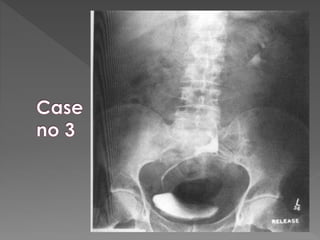

X ray films 1)Pre contrast 2) 5 mins 3) 25 mins 4) Post void

 The plainfilm demonstrates calcification within distended upper pole calyces